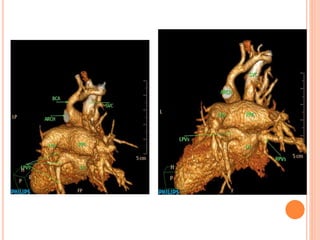

CASE #2 8MONTH-OLD GIRL